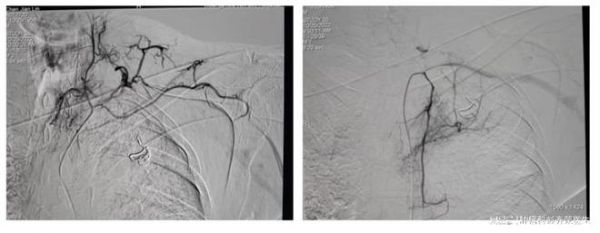

对于陈大伯的情况,肿瘤科一区给予以了护肝、护胃、补液、营养支持等对症处理,以及动脉灌注栓塞治疗等抗肿瘤微创治疗,以保证陈大伯能在治疗期及康复期保持理想体重,增加疾病抵抗力、减少因性疲劳的发生、提高生活质量。

近日,陈大伯再次返院行第二次疗程治疗,在经过一次微创综合治疗过后,陈大伯的疼痛得到了明显缓解。